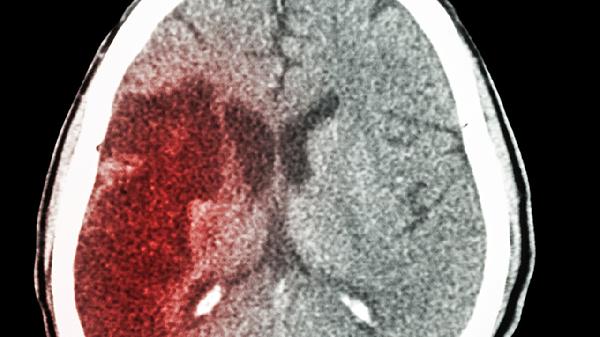

头晕眼花不一定是没睡好!当身体发出这7个警.报信号,可能是大脑在“喊救.命”。别以为只有老年人才会脑供血不足,现在越来越多的年轻人也开始出现这些危险征兆。想要远离脑梗和痴呆的威胁,这几件事现在就要做起来!